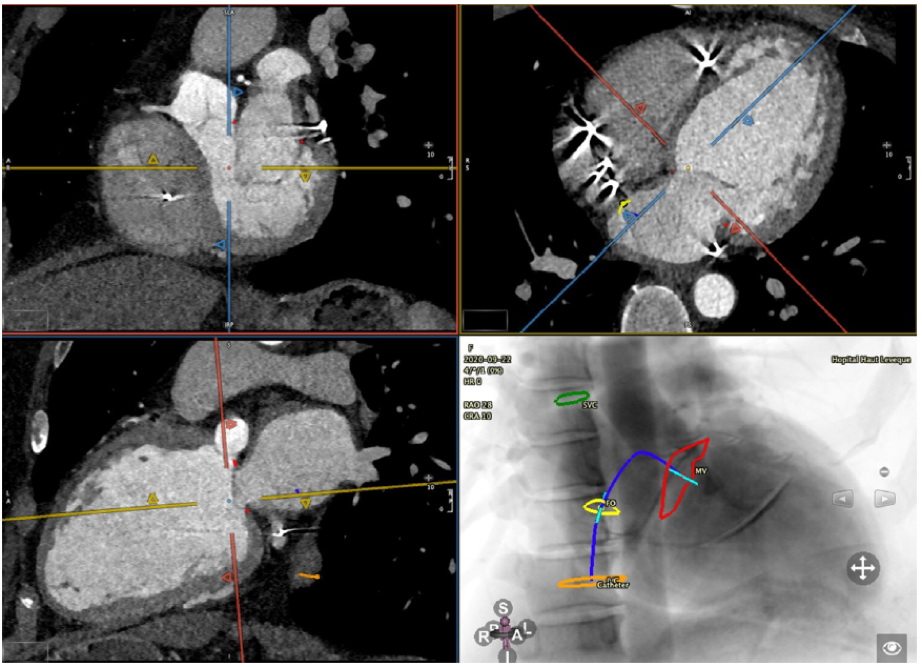

经导管二尖瓣修复术中的多模态成像

图3.心脏计算机断层扫描分析显示经中隔导管路径规划。

FO:卵圆窝;IVC:下腔静脉;MV:二尖瓣;SVC:上腔静脉。

由于其高空间分辨率和显示相邻心脏结构之间解剖关系的优越性,计算机断层扫描CT已成为TMVr之前的一种重要成像方式。这些能力与经导管二尖瓣(MV)瓣环成形术尤其相关,在该手术中,三维解剖学在尺寸分析、器械尺寸和手术规划期间的导管过程方面对二维技术提出了挑战。此外,需要评估冠状窦(CS)和回旋动脉与二尖瓣环的关系,因为它可能会影响手术效果(例如,高行程冠状窦(CS)会损害间接环成形装置的效果)和并发症(例如,回旋动脉撞击)(图3)。